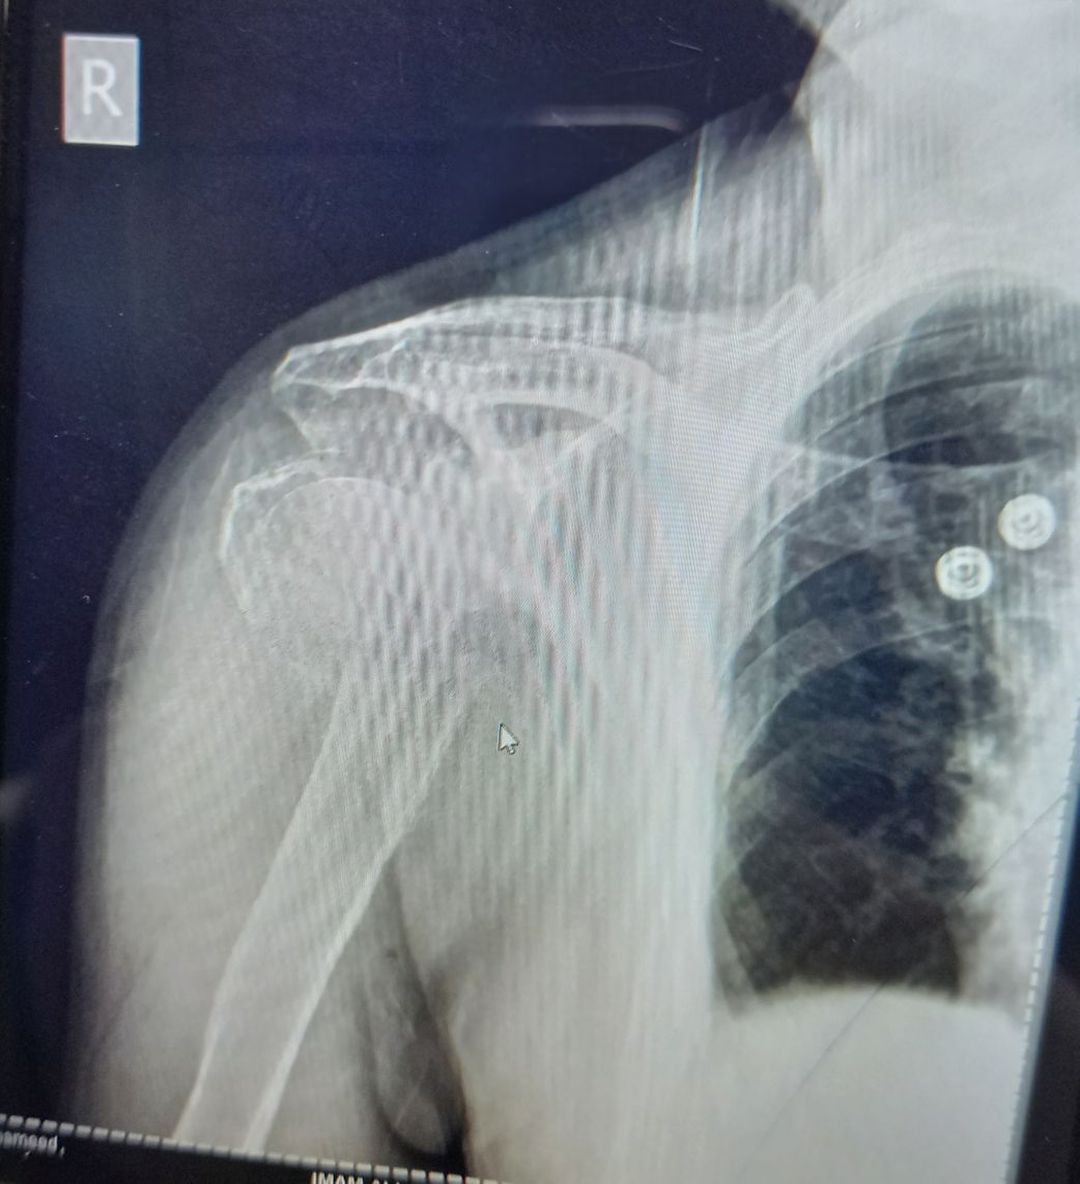

Head of humerus

Fractures

Humerus

Shoulderdislocation